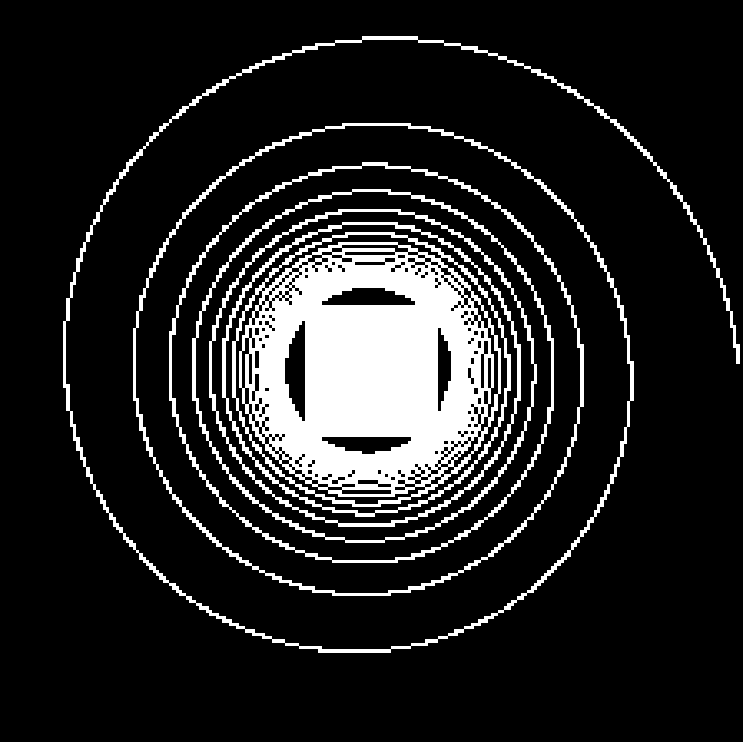

Using the same method as in 2D, namely TSP-sampling and projection onto the set of constraints, we reconstructed volumes from 3D -space. In order to estimate the quality of the reconstructions, we compared the angiograms computed from the 3D images using Frangi filtering [19]. The results are shown in Fig. 3 for acceleration factors (Fig. 3(b,e)) and (Fig. 3(c,f)) and compared to the angiogram computed from the whole data.

Using the strategy described in Part 3.1 the time to traverse -space would be 3.53 s (full acquisition), 3.15 s () and 0.88 s (). The main drawback of TSP-based sampling schemes is that the time reduction is not directly proportional to , in contrast to classical 2D downsampling and reading out along the third dimension. Nevertheless, if the number of measurements is fixed, the TSP-based approach leads to more accurate reconstruction results since the sampling scheme may fit any density [7].

Angiograms shown in Fig. 3 illustrate that one can reduce the travel time in the -space and still observe accurate microvascular structure. If , time reduction is minor (about 10% less), but the computed angiogram is almost the same as the one obtained with a complete -space. It is interesting to notice that with a higher acceleration factor (), the acquisition time is reduced by 75%, but the computed angiogram remains of good quality. The angiogram appears a bit noisier, especially in the pre-injection setting (Fig. 3(c)), but the post-injection image allows recovering Willis polygon and most of the major vessels of the mouse brain (Fig. 3(f)).

| Original (s) | (s) | (s) |

| PSNR=29.0 dB | PSNR=26.6 dB | |

| PSNR=25.5 dB | PSNR=24.1 dB |